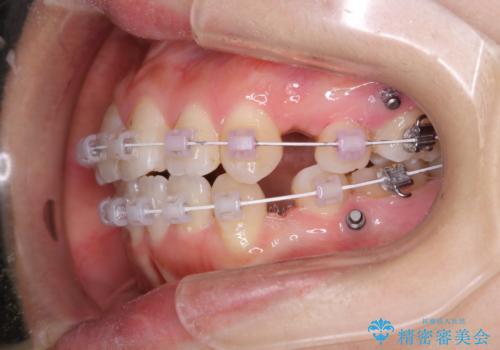

- ワイヤー矯正中のメンテナンスでPMTCを希望されました。染め出しを行い、歯ブラシ指導とPMTC30分コースを行いました。

毎日しっかりと磨いているようでも、装置の周りや歯と歯の間・歯と歯茎の間に磨き残しが残ってしまいます。そのため磨き残しをチェックする『染め出し剤』を使用すると明確に磨き残しを見ることができます。

染め出されている部分の磨き残しは、毎日の習慣として歯ブラシをしていてもいつも磨けてない部分です。